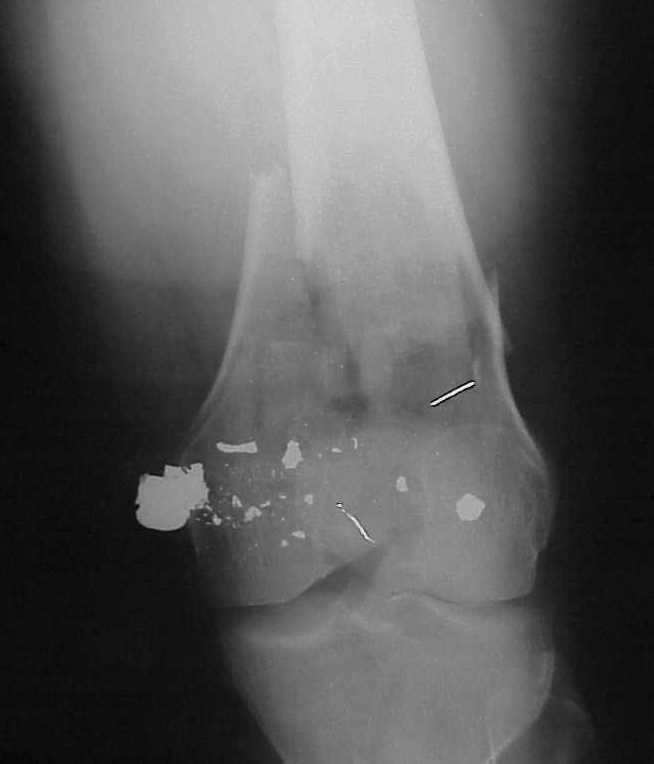

A CT and knee xrays would help identify lateral condyle comminution and/or a "hoffa fragment" of the posterior condyle. I am concerned that the lateral cortex is not sufficient to give purchase for a retrograde IMN. blocking screws could improve this as a possibility. A long blade or LISS if avaible would be my secondary choices. Good luck. Any chance you can get these cases transferred earlier when it

See attached case that was done several years ago before LISS. He had comminuted trochlea and anterior blocking screws were used to prevent anterior IMN cut-out.